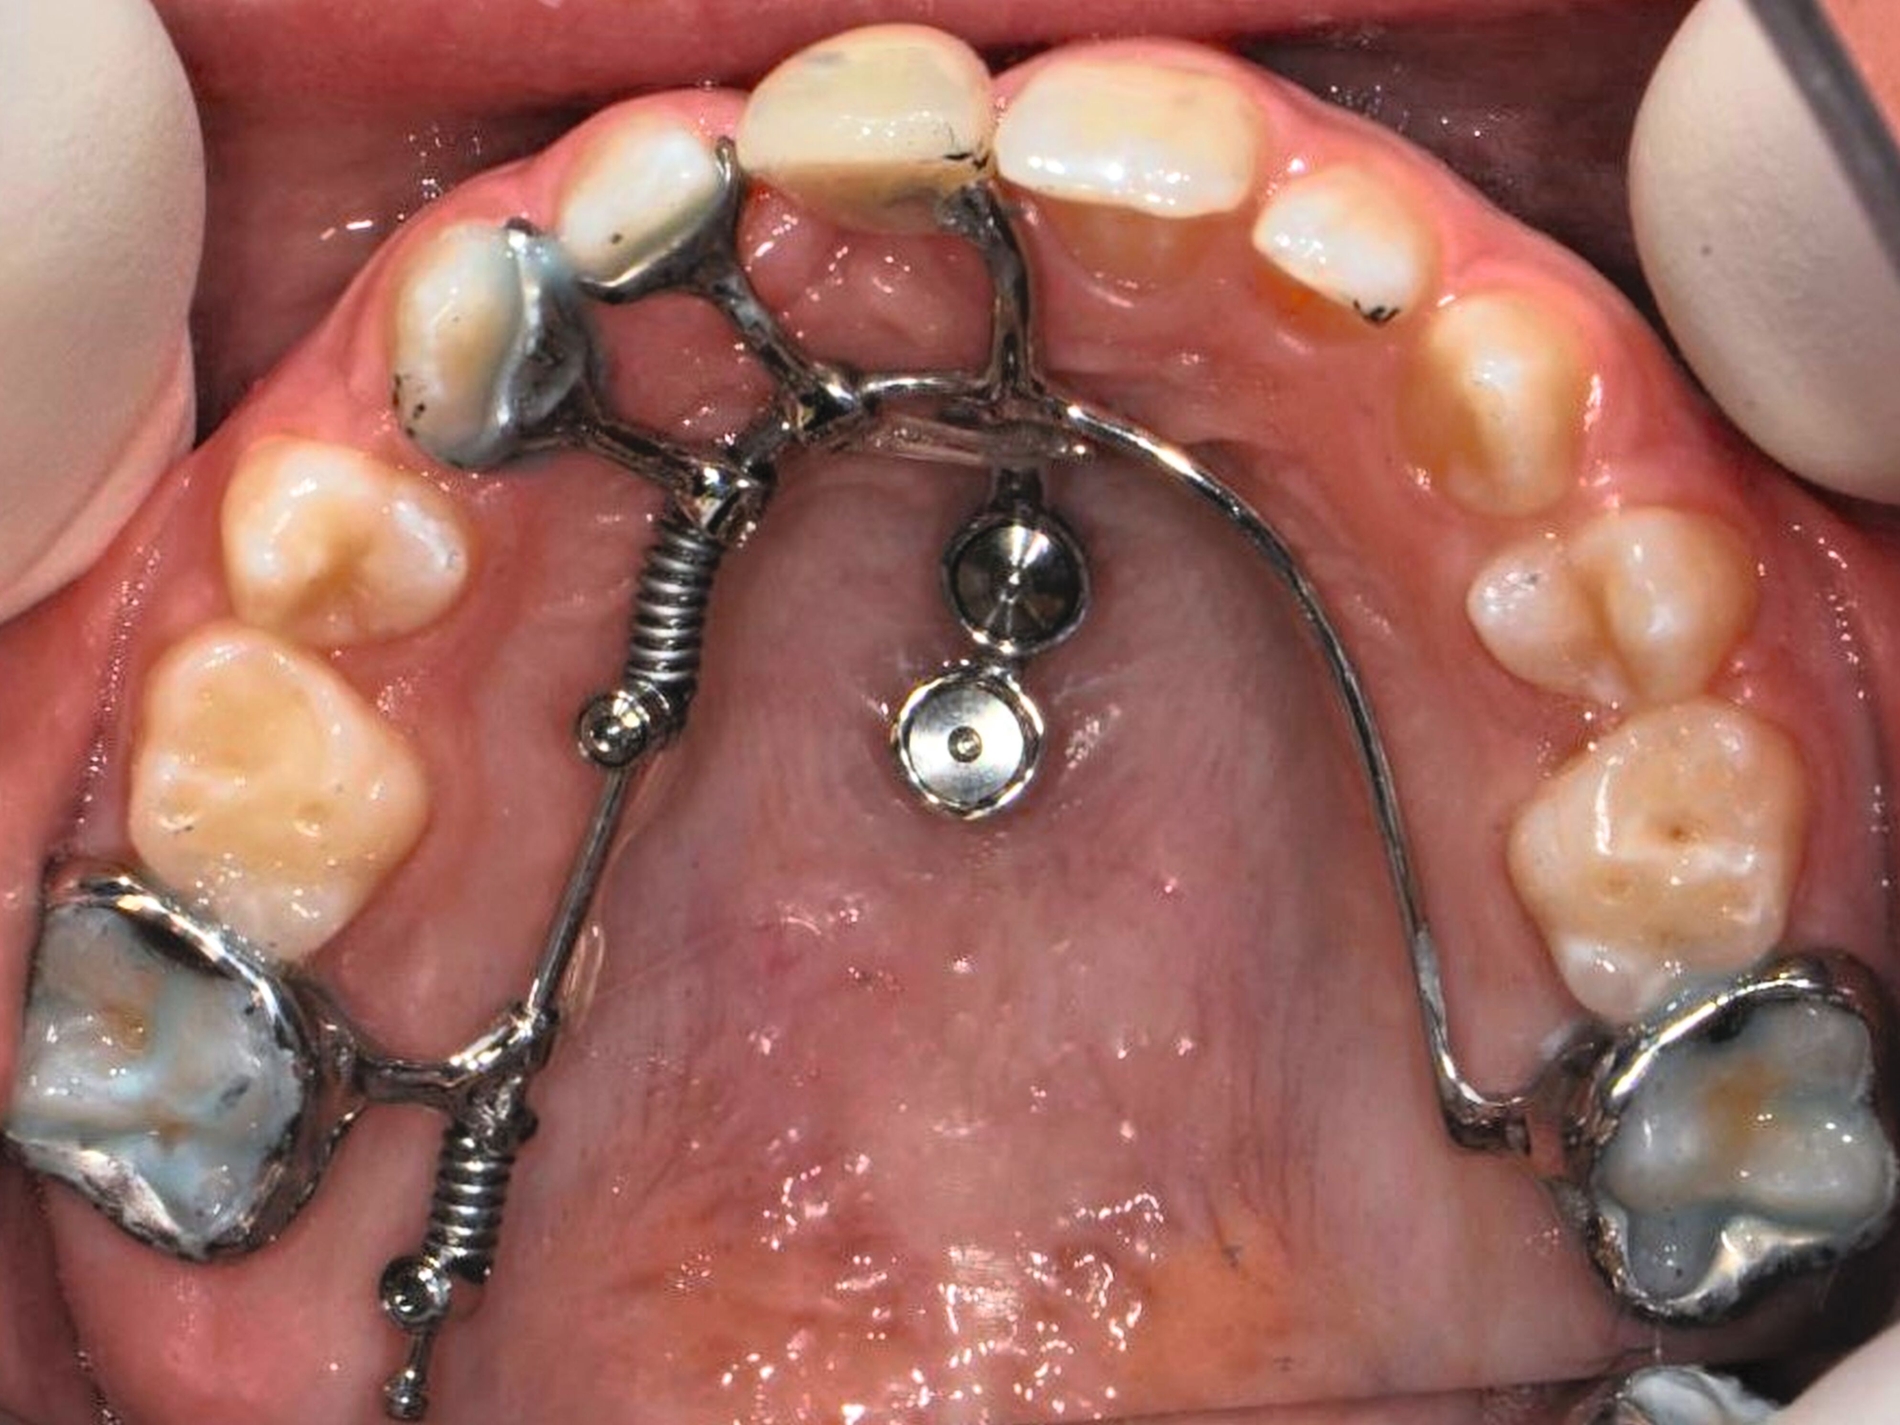

Beispielsweise kann durch eine kieferorthopädische Mesialisation nicht traumatisierter Nachbarzähne auch im wachsenden Kiefer ein traumatisch bedingtes Knochendefizit günstig beeinflusst werden [Pontoriero et al., 1987; Prapas et al., 2008; Stenvik und Zachrisson, 1993] (Abbildung 4).

Durch den Einsatz skelettaler Verankerungshilfen ist es möglich, auch in komplexeren Situationen einen kieferorthopädischen Lückenschluss durchzuführen. Mit digitalen CAD/CAM-Herstellungsmethoden wie dem selektiven Laser-Melting-Verfahren können hochindividualisierte Apparaturen angefertigt werden, die verschiedene Behandlungsaufgaben gleichzeitig adressieren beziehungsweise mit deren Hilfe Kraftvektoren präzise geplant und appliziert werden können.

Zu den weiteren Vorteilen gehören die geringeren Nebenwirkungen auf die Nachbarzähne, die bessere Planbarkeit bei Set-up-basierten Apparaturen, die gute Pflegbarkeit, die einfache Handhabung, die Verkürzung der gesamten Behandlungszeit durch reduzierte Multibracket-Phasen sowie die geringere Beeinträchtigung der orofazialen Ästhetik (Abbildung 5).